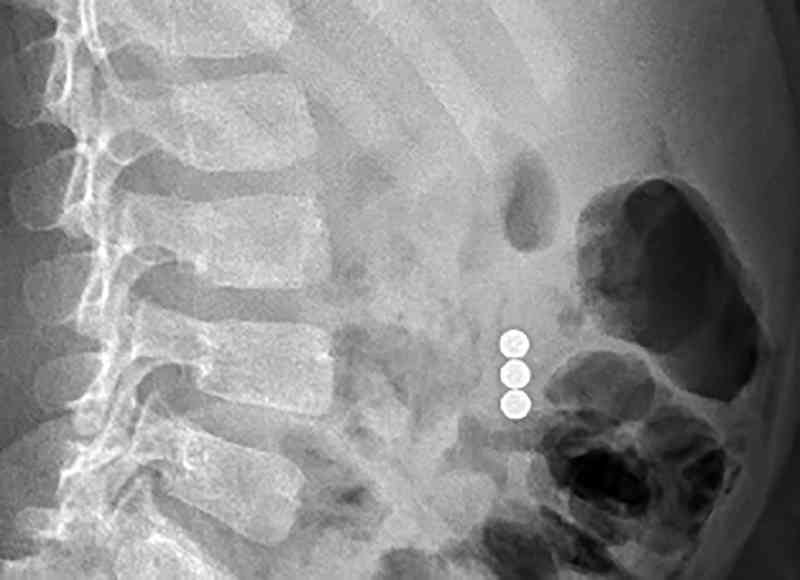

٥-الالعاب المحتوية على قطع مغناطيسية

من أخطر الالعاب

عند ابتلاع قطعة واحدة لا يوجد ضرر

ابتلاع قطعتين واكثر يؤدي الى التصاقات في الامعاء يسبب تهتك جدار الامعاء وخروج الفضلات لتجويف البطن ما يسبب الوفاة وقد ذكرت سابقاً انه مر علي شخصياً ٣ حالات انتهت جميعها بوفاة الطفل للأسف